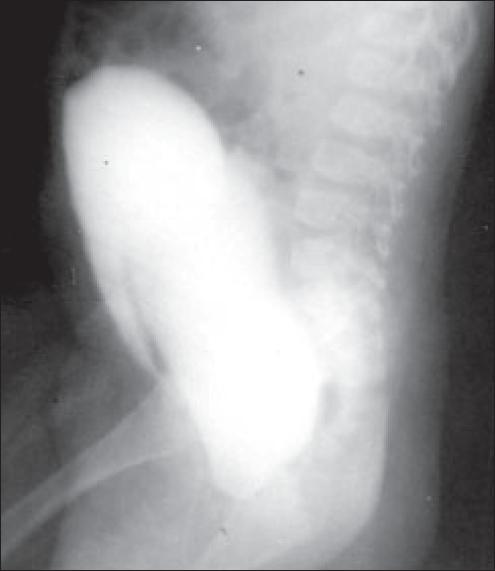

An unusual case of urinary tract obstruction due to imperforate hymen in an 11-month-old infant.

Variations in the anatomy of the hymen are common and imperforate hymen is an extreme manifestation. In spite of the recommendations for early inspection of the external genitalia, hymenal malformations escape diagnosis until the time of menarche. Rarely, female infants with imperforate hymen present with urologic complications. We would like to present an unusual case of urinary retention in an 11-month-old female infant due to imperforate hymen. This infant was successfully treated surgically.